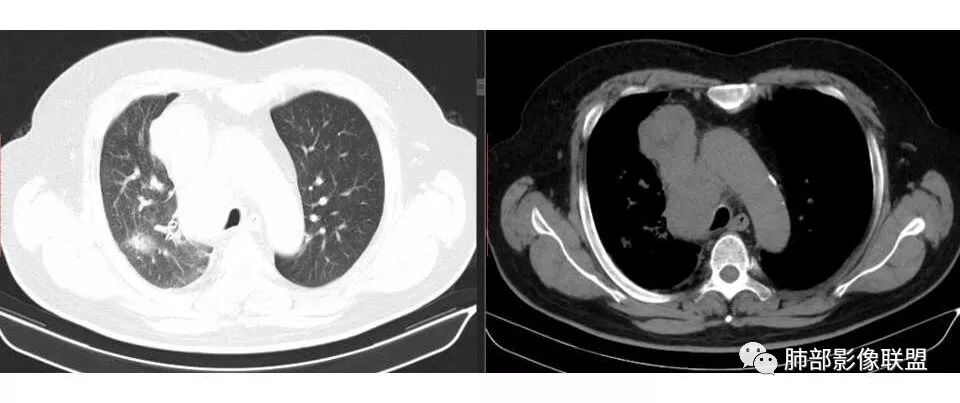

张帅: 患者以肢体无力就诊,既往有吸烟史,胸CT:右肺门占位性病变,密度不均,病灶内病灶内支气管明显狭窄,走行僵硬,病灶边缘光滑,呈浅分叶,未见明显毛刺,对中叶支气管明显挤压。右肺内可见散在片状实变影,前纵隔淋巴结明显肿大,内可见低密度区,2r 4r 7 10r淋巴结明显肿大。诊断考虑恶性方向,肺癌(小细胞)并纵隔肺门淋巴结转移?淋巴瘤?

王秀仙: 右肺门肿块,中间段支气管壁增厚,管腔狭窄,上叶支气管开口截断,周围肺组织可见斑片影及小叶间隔串珠状增厚,纵膈淋巴结肿大并见低密度坏死,考虑鳞癌。鉴别小细胞肺癌

局限性中央间质增厚,考虑癌性淋巴管炎

右侧胸膜增厚

1.右肺上叶不规则结节影,右肺门及纵隔多结节并形成巨大块影,密度均匀,沿途支气管明显狭窄。

原发灶小或隐匿,肺门纵隔淋巴结异常增大,所谓“娘小崽大”常见于肺小细胞癌!

2.右肺小叶间隔增厚伴微小结节,提示癌性淋巴管炎。

3.注意患者年年体检未见明显异常!

一年之内,甚至几个月内出现的肺部肿块,也几乎将鳞癌、腺癌、类癌、肉瘤等肺原发肿瘤彻底排除在外!